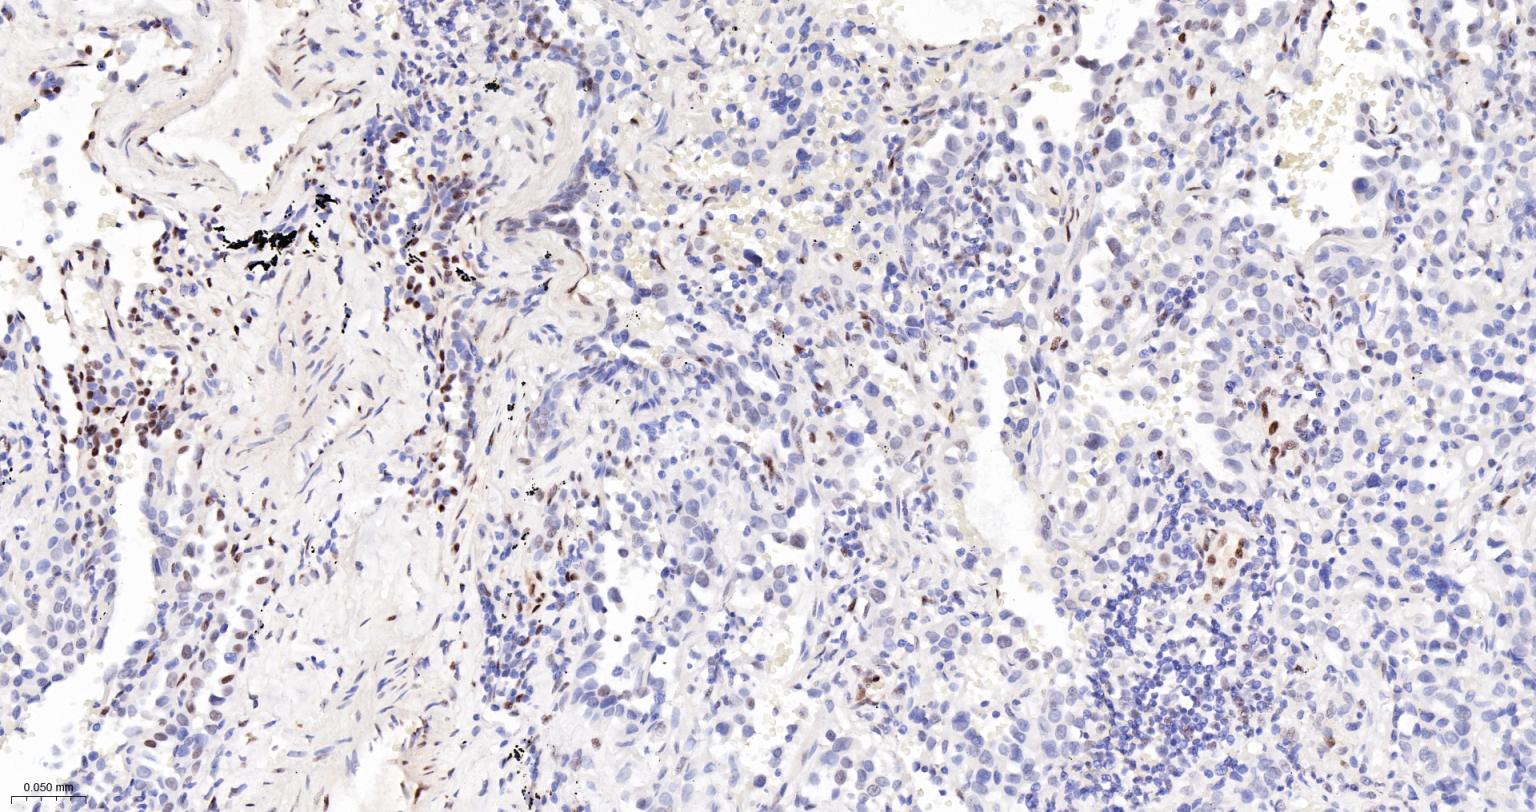

Paraformaldehyde-fixed, paraffin embedded Human Tonsil; Antigen retrieval by boiling in sodium citrate buffer (pH6.0) for 15 min; Antibody incubation with phospho-STAT3 (Tyr705) Monoclonal Antibody, Unconjugated(bsm-33301M) at 1:200 overnight at 4°C, followed by conjugation to the bs-40296G-HRP and DAB (C-0010) staining.